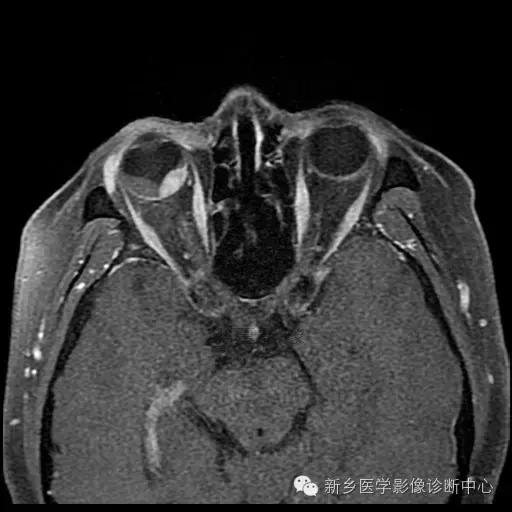

脉络膜黑色素瘤

脉络膜黑色素瘤是由恶性黑色素瘤细胞组成的神经外胚叶性肿瘤, 其组织发生于脉络膜基质内的黑色素细 胞, 国内发病率仅次于发生在儿童的视网膜母细胞瘤, 居眼内肿瘤的第二位, 少数病例可向眼眶蔓延, 晚期向肝脏转移,老年人居多。

影像:

(1)CT:早期眼环局限性增厚;突入玻璃体腔后, 表现 为 密度均匀、边界较清楚的等密度或略高密度半球形或球形肿块;肿瘤较大时,外形不规则, 可占据整个玻璃体腔。可侵犯巩膜外、视神经,可继发视网膜脱离。

(2)MRI:肿瘤边界光 整, 多呈蘑菇型,T1WI呈高或极高信号,T2WI呈低信号。增强扫描肿瘤强化而视网膜及脉络膜下积液及眶内脂肪不强化。